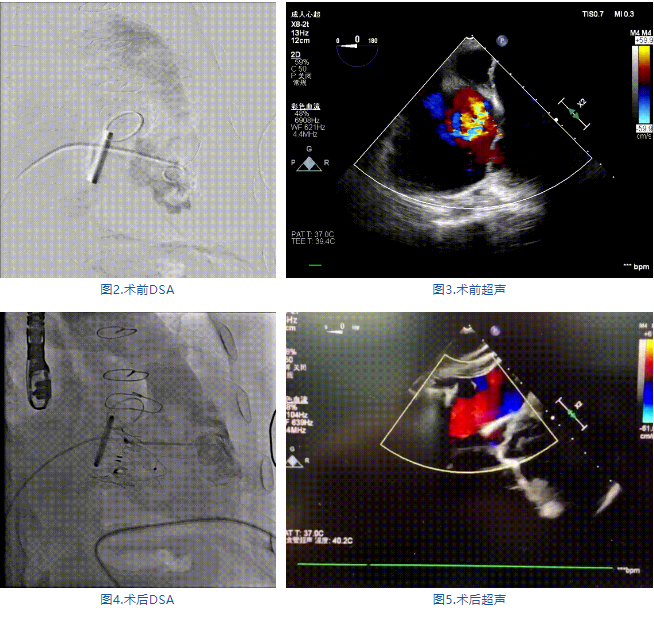

手術(shù)在全麻狀態(tài)下進(jìn)行,郭惠明教授團(tuán)隊(duì)采用經(jīng)右側(cè)頸靜脈入路的方式送入輸送器進(jìn)入體內(nèi),并在TEE和DSA的指引下進(jìn)行。在輸送器進(jìn)入右室后釋放室間隔錨定裝置,旋轉(zhuǎn)輸送器,使得錨定裝置對(duì)準(zhǔn)室間隔面;而后釋放前瓣夾持件,確定夾持件位于右室側(cè)釋放LuX-Valve Plus人工瓣膜盤片,再使用DSA和超聲確認(rèn)盤片是否位于右房側(cè),同時(shí)調(diào)整瓣膜的同軸性。緊接著在DSA和超聲的監(jiān)視下調(diào)整室間隔錨定件貼合室間隔,釋放室間隔錨定裝置。再次確認(rèn)瓣膜的穩(wěn)定性和同軸性后,將輸送器撤出體內(nèi),最終完成LuX-Valve Plus人工瓣膜植入(圖2-5),手術(shù)獲得圓滿成功。患者在手術(shù)室即刻拔除氣管插管,術(shù)后超聲提示LuX-Valve Plus人工三尖瓣瓣膜同軸性良好,瓣架固定牢靠,無反流和瓣周漏。